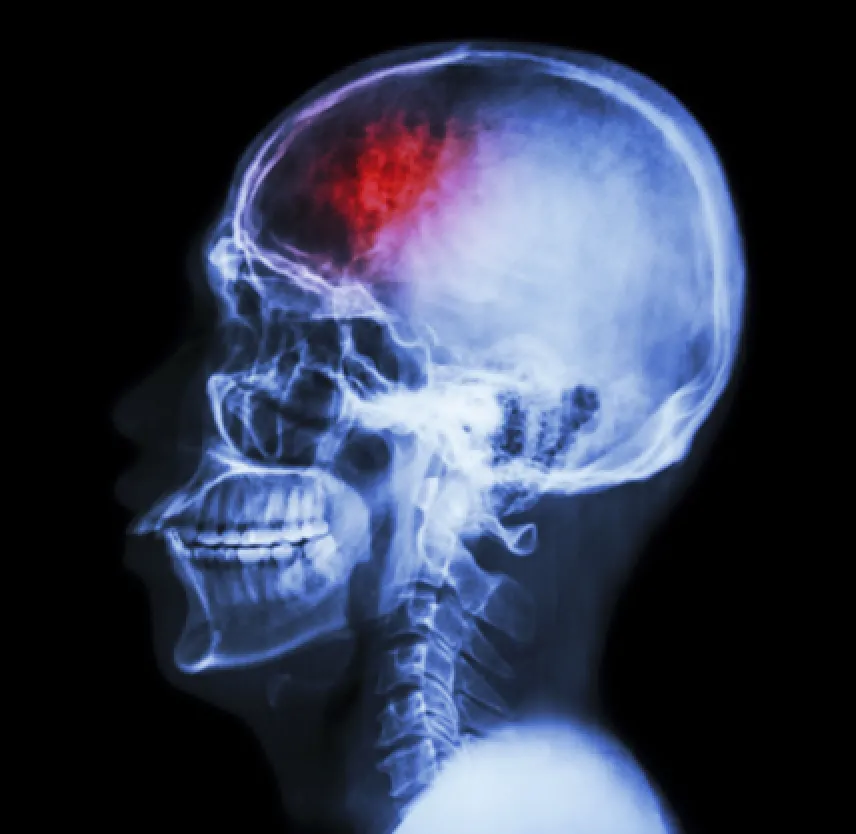

Brain injuries require medical treatment. Doctors commonly use MRIs and CT scans to see if there is permanent damage or bleeding in the brain. Mild to moderate brain injuries are treated conservatively with medication and rest. Diuretics, anti-inflammation medicines, anti-seizure drugs and pain medication are used to alleviate symptoms. If there is bleeding in the brain or a skull fracture, surgery may be a life- saving option that doctors use for treatment.